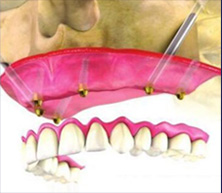

“穿颧种植术”是一种通过颧骨固定种植牙,将种植体植入到位于人面中部前,眼眶的外下方呈菱形较硬的骨头——颧骨,被种植牙界誉为“珠穆朗玛峰”的顶级技术,俗称“无土栽培术”

“穿颧种植术”受力效果好,稳定性强,可避免或减少术中大量植骨的风险,适用于上颌骨切除、上颌骨严重萎缩,常规内外提升也无法达到种植条件的无牙颌患者......查看详情